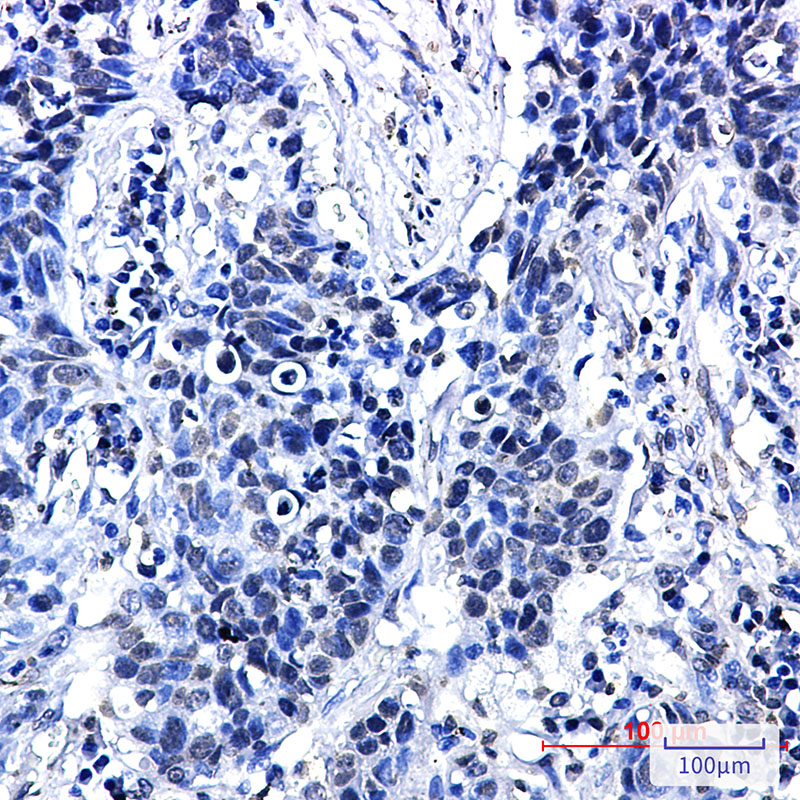

Immunohistochemistry analysis of paraffin-embedded Human lung cancer using Phospho-delta 1 Catenin/CAS (Thr916) antibody.High-pressure and temperature Sodium Citrate pH 6.0 was used for antigen retrieval.